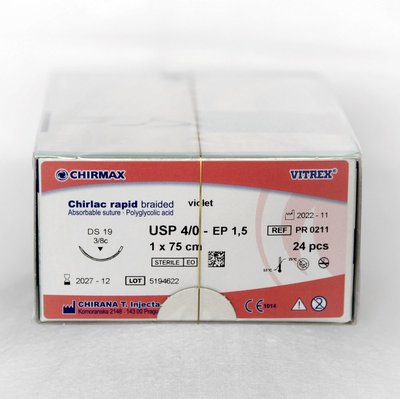

CHIRLAC rapid braided HR 18, 1,5 EP - 4/0 USP, 1 x 75 cm, 24 ks

CHIRANA T.InjectaBalení: 24 ks

Balení: 24 ks

| Značka | CHIRANA T.Injecta |

| Dodavatel | Medident Sk |

| SKU | CHIR PR0256 |

| Kategorie | Ordinace > Chirurgie > Šití > Vstřebatelné |